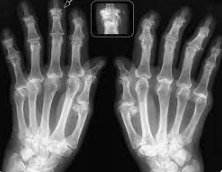

frequentemente colpite sono quelle maggiormente sollecitate dal peso e dall’attività, tra cui ginocchia, anche, spalle, mani, piedi e colonna vertebrale. Con il processo degenerativo dell’artrosi si assiste a un assottigliamento della cartilagine articolare e in seguito a deformità ossee che causano il dolore e i sintomi specifici dell’artrosi, particolarmente evidenti a livello delle falangi distali delle mani, per esempio.